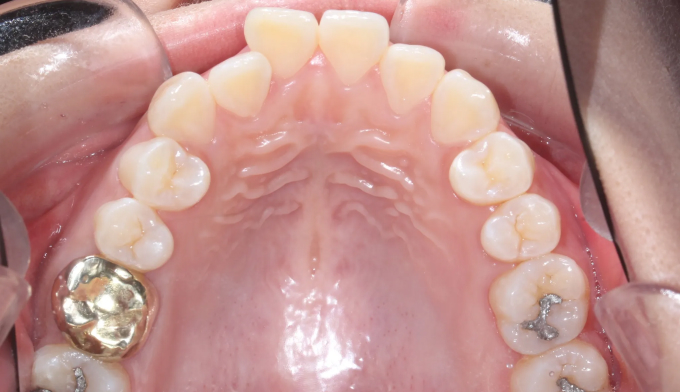

개방교합은 양쪽 어금니가 잘 맞닿아 있는데도 앞니가 위아래로 떠서 맞물리지 않는 경우를 말합니다.

이 케이스는 앞니의 치열도 불규칙합니다.

미니스크류를 이용하여 어금니 교합을 변화시켜 개방교합을 해소하였습니다. 이와 동시에 어금니의 후상방 이동으로 앞니 배열공간을 만들었고 앞니를 가지런하게 배열시킬 수 있었습니다.